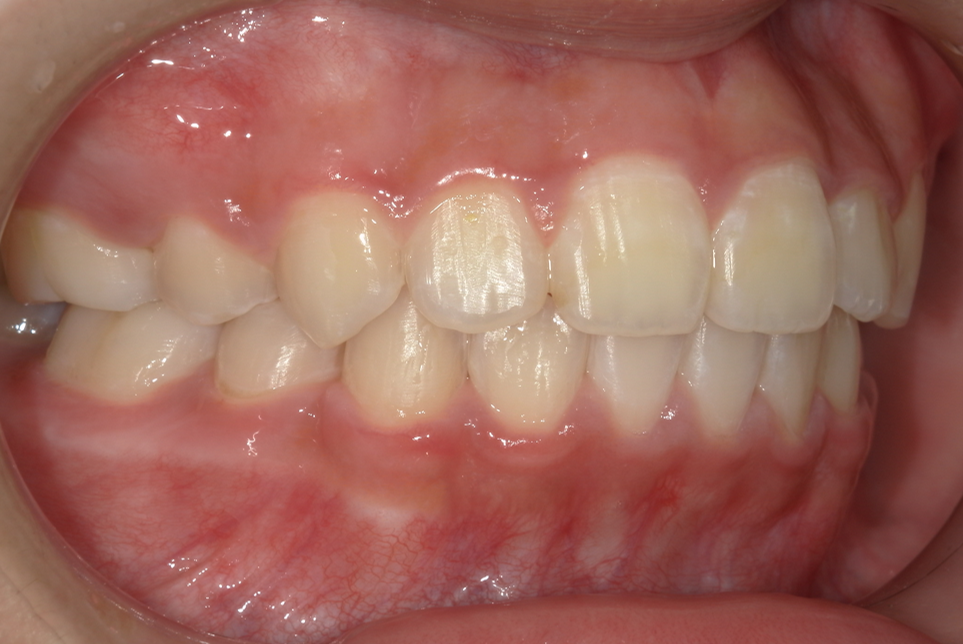

case2.10代女性・歯のデコボコとクロスバイトを改善したい

術前①:正面

| 主訴 | 歯並びを良くしたい |

|---|---|

| 診断名・主な症状 | 上下顎叢生。クロスバイト |

| 年齢 | 10 代 |

| 治療に用いた主な装置 | 全顎ブラケットを装着。途中バイトアップしてクロスバイトの改善 |

| 抜歯有無・抜歯部位 | なし |

| 治療期間 | 1 年 5 か月 |

| 治療費用 | 70 万円 |

| リスク・副作用 | 後戻り防止の為、将来、親知らずの抜歯をする |